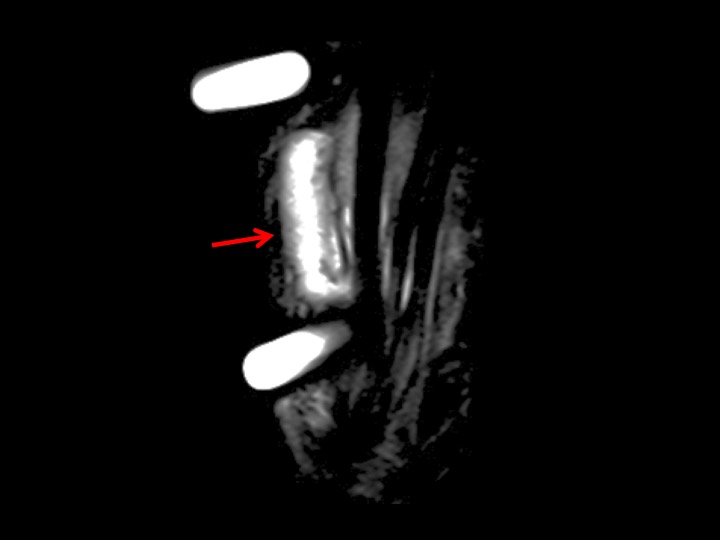

54F 2 months dorsal pain and swelling, suspect ganglion

The mass is centered over the CMC joints, and corresponds to stenosing tenosynovitis of the 4th extensor compartment. There is no ganglion (more commonly in proximity to the SLL). At the level of carpus, there is tendinosis and probable partial tearing of multiple common extensor tendons. At the level of the radiocarpal joint, all of the EDC tendons clump together, with enhancement of the thickened extensor retinaculum. There is pre-and post- stenotic dilation with effusion and enhancing synovium in the wrist and hand. This was referred by a hand surgeon. I have seen many cases like this on MRI and US and am always amazed that there is no suspicion of stenosing tenosynovitis and that ganglion is favored. I would imagine there would be painful limitation to finger extension. In this patient, there is no joint narrowing or articular synovitis. I have noticed this more commonly in women and am intrigued that the attached article implies that there may be some association to estrogen stimulation and deficits. Reference article.

4th extensor compartment tendinosis and stenosing tenosynovitis